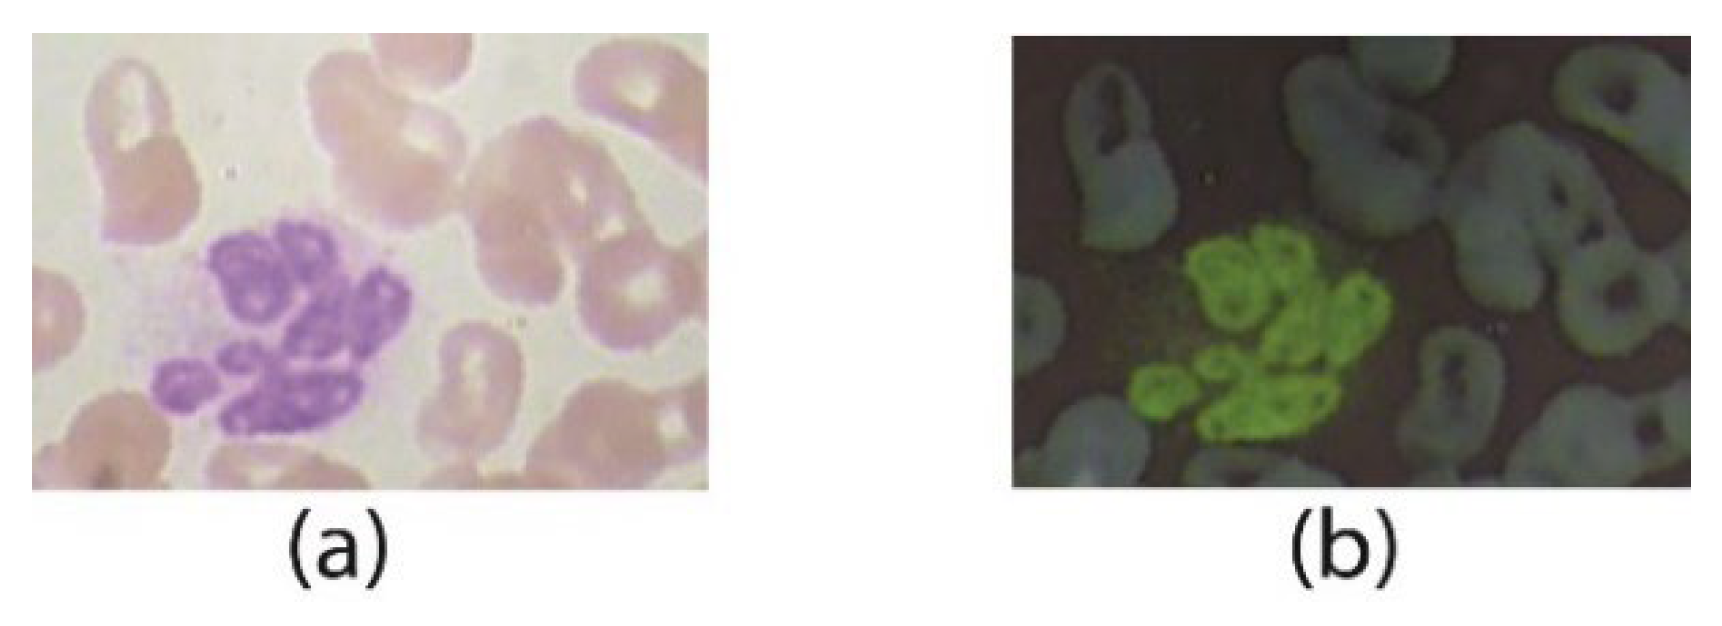

4.1. Dataset

The publicly available dataset ALL-IBD is used for the parametric evaluation of the proposed method. ALL-IBD contains four classes of WBCs listed in Table 1 as (a) the eosinophils, (b) is the type neutrophils, (c) circular-shaped nucleus type is lymphocytes, and (d) is monocyte. The four classes contain approximately 2400–2500 samples per class with 9954 images in total.

All images are in RGB format, having images of size 320 × 240. Figure 14 illustrates some sample images of the dataset. The dataset images contain some extra background portions.

Figure 14.

WBCs classes: (a) eosinophil, (b) neutrophil, (c) basophil, (d) monocyte.